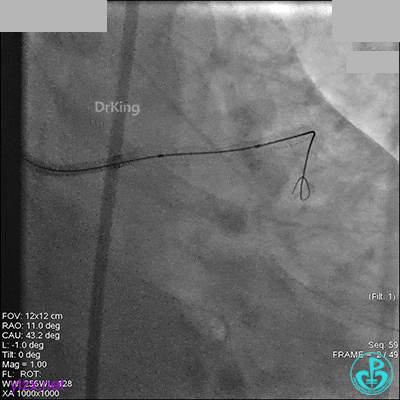

右冠脉中段充分扩张后欲植入3.5×38mm支架时,支架难以通过中远段扭曲处,且指引导管、导丝弹出飞扬。反复尝试导丝重新到达右冠脉远端时通过不顺利,局部造影剂滞留,远端血流接近3级。

右冠脉血流3级,患者无症状,终止手术。